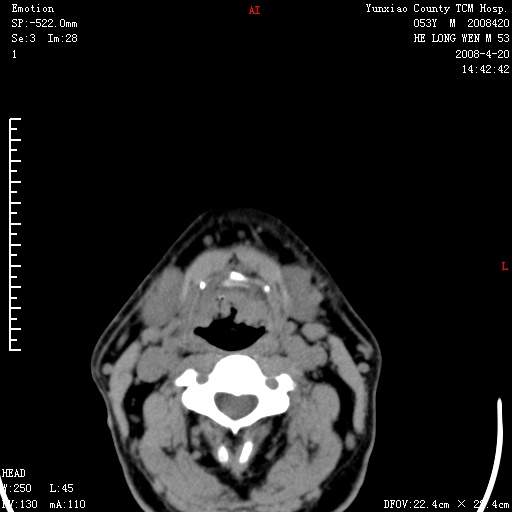

双侧扁桃体肿大:考虑化脓性扁桃体炎。

双侧扁桃体肿大 ,考虑扁桃体炎。

双侧扁桃体肿大,建议结合临床!

双侧扁桃体肿大 ,考虑扁桃体炎

应该有症状,体检此部位不是常规体检项目,支持双侧扁桃体肿大 ,考虑扁桃体炎,但还是强化一下吧。

双侧扁桃体肿大,考虑扁桃体炎,应做一下增强

显示部分为舌扁桃体,腭扁桃体未见显示。会厌显示欠规则,建议喉镜。